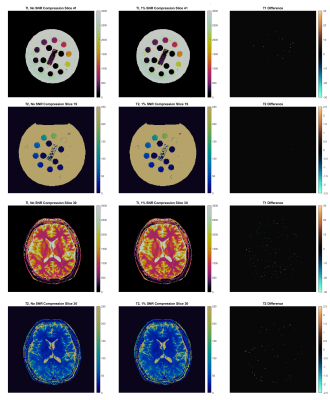

Figure 4 demonstrates the differences in T1 and T2 maps caused by SNR-constrained data compression.With compression disabled, phantom reconstructions finished in 52 seconds with mean network throughput of 138Mbps, versus 54 seconds and 70Mbps at 1% SNR compression error tolerance. Versus the maps generated with uncompressed data, compression introduced 0.00±0.09% error in T1 values and 0.00±0.04% error in T2 values.

Comparison of reconstructions performed on uncompressed versus compressed raw datasets for both a phantom and in-vivo acquisition. In the phantom data, compression introduced 0.00±0.09% error in T1 values and 0.00±0.04% error in T2 values versus the uncompressed data, while in-vivo compression introduced 0.01±0.2% error in T1 values and 0.02±1.17% error in T2 values.